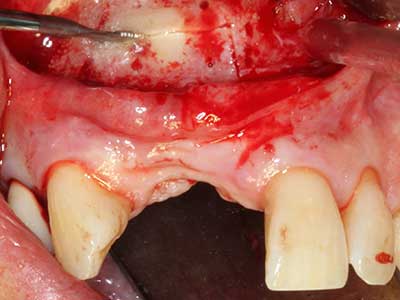

When surgical procedures are performed on bone in the immediate vicinity of sensitive structures such as blood vessels or nerves, rotary instruments pose a significant risk of iatrogenic injury. Piezoelectric devices can be helpful for preparation of bone covers and removal of hard tissue close to nerves, particularly for exposure of nerves after iatrogenic injury but also during nerve lateralization for resective and reconstructive procedures or implant placement (Fig. 17-20). Light contact between the piezotip and the nerve does not generally result in damage but proceeding incautiously with saw-like motions or attachments where a residual bone substrate remains may cause temporary or even permanent nerve damage. However, the risk of damage is considered to be substantially lower than when using saws or milling instruments (Pereira, Gealh et al. 2014).